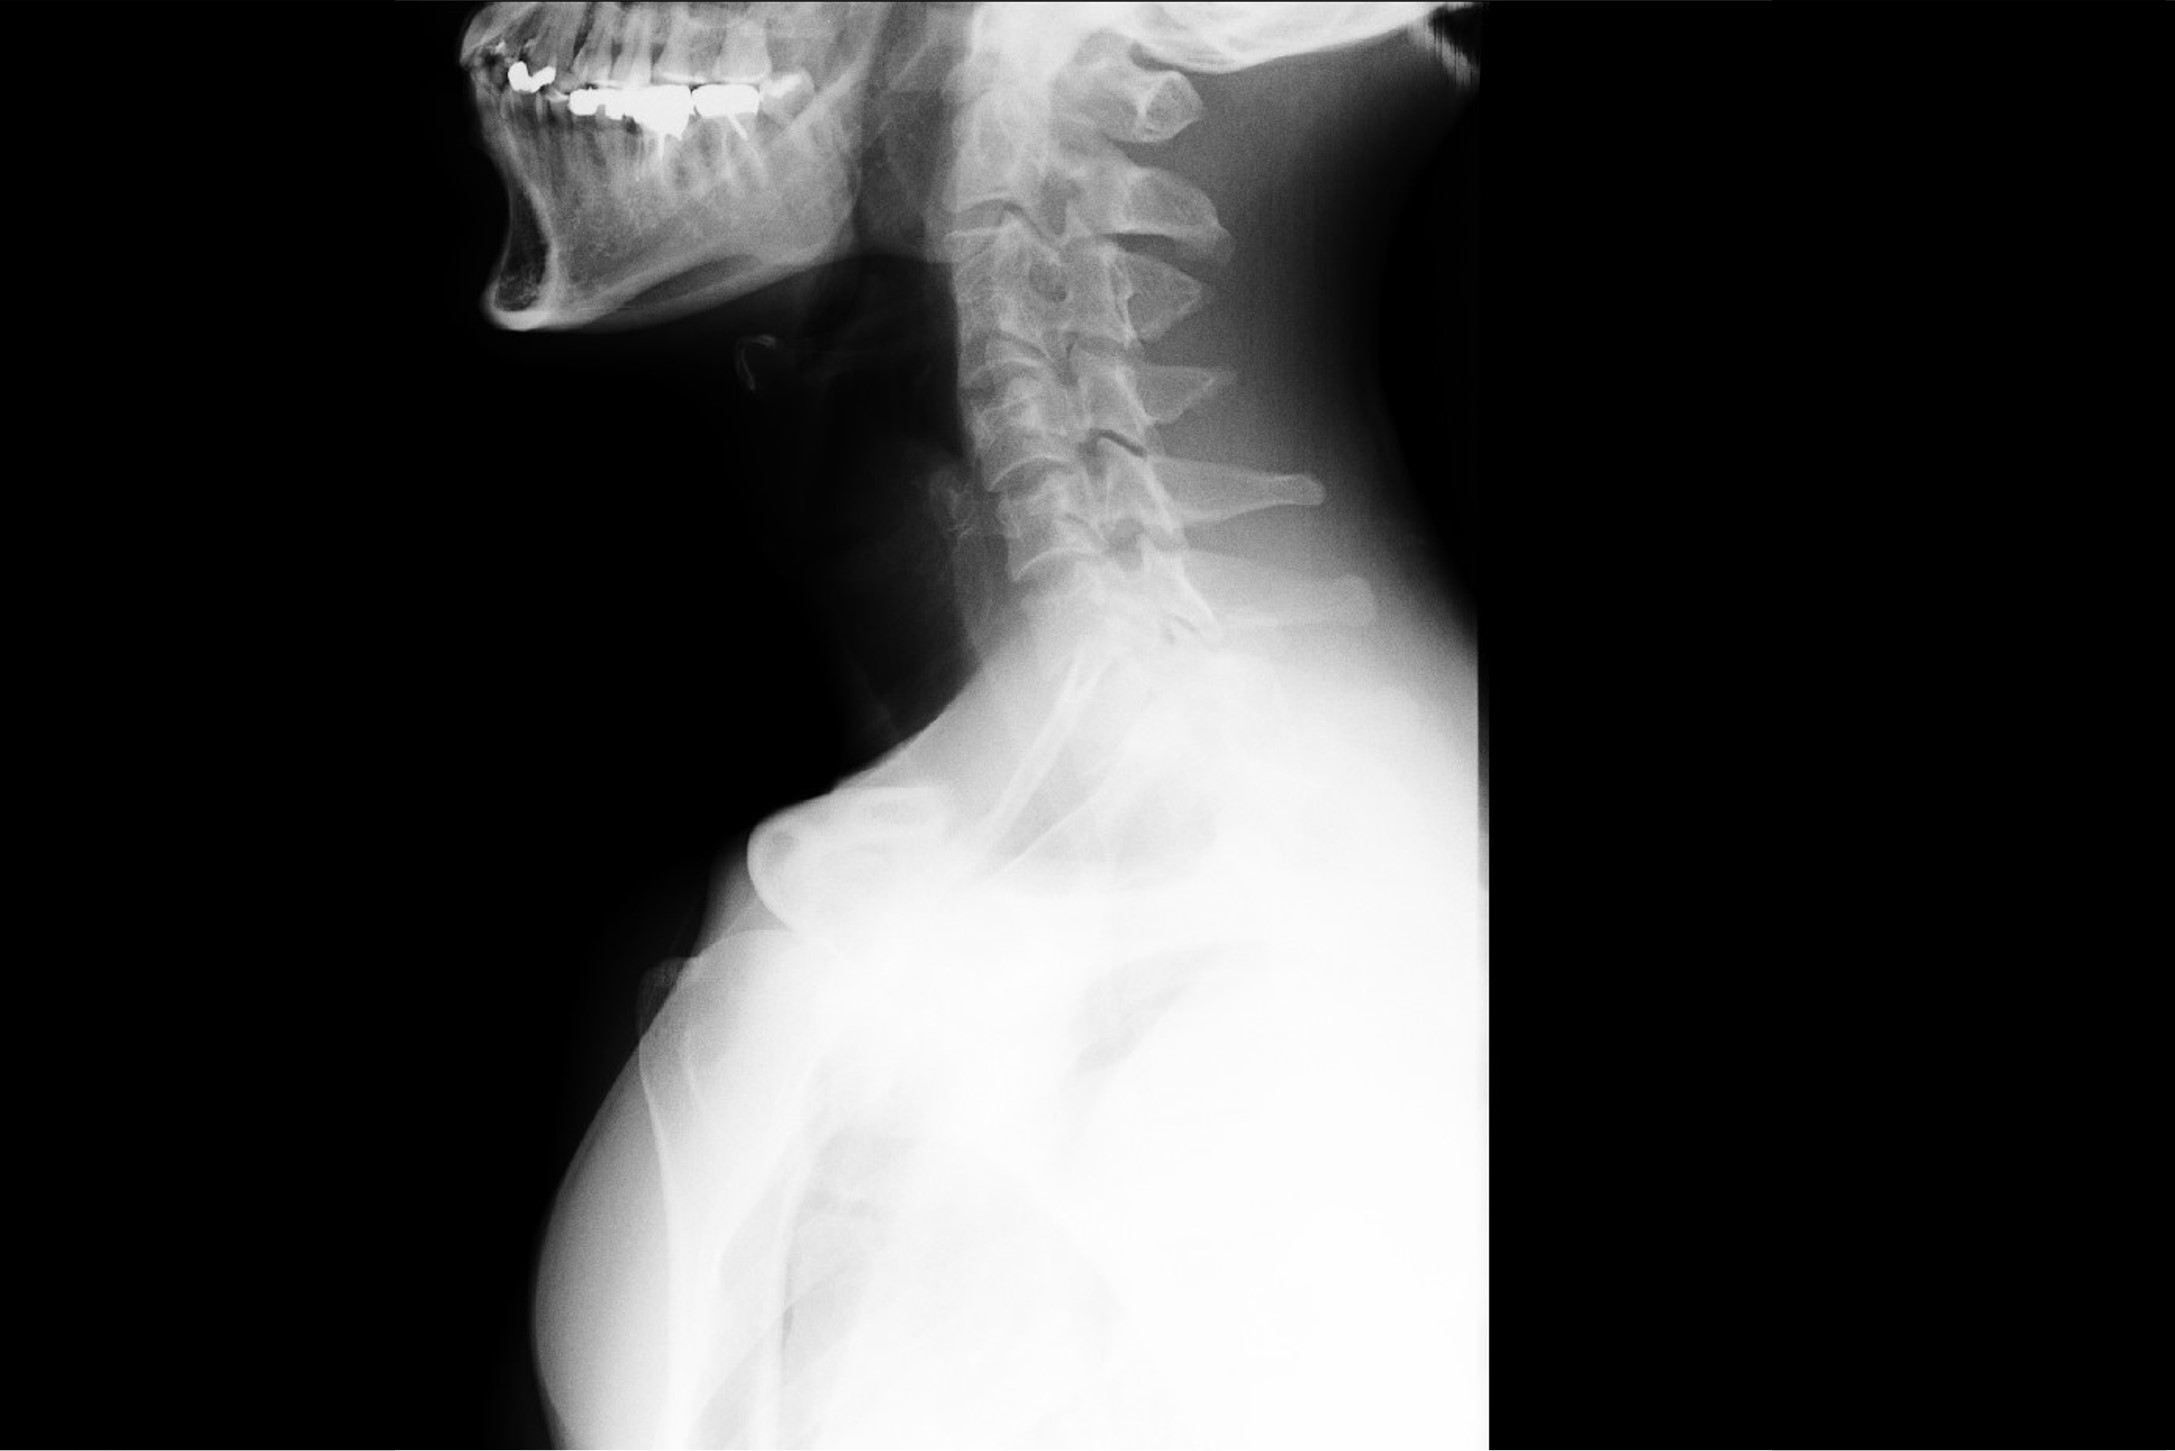

- 首痛:長時間スマホやPC、運転姿勢の影響による